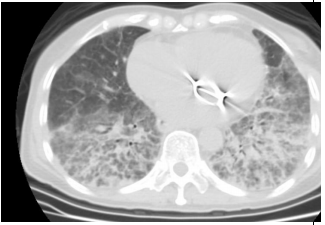

17. 63歲女性病人因風濕性心臟病換過二尖瓣瓣膜,心律不整長期使用藥物。因為喘的情形加劇,CXR及電腦斷層如圖示,下列何者為是? (A) 為典型的 Interstitial Lung Disease,可以是idiopathic pulmonary fibrosis。 (B) 肺部有許多小點,Miliary TB無法排除。 (C) X光及電腦斷層有許多的線條,可以是kerley line 應為肺水腫。 (D) 無顯影劑肝臟卻明顯較亮要考慮Amiodarone 造成的 Interstitial Lung Disease。 (E) 有許多的點跟線,應考慮肺癌合併 lymphangitis carcinomatosis。